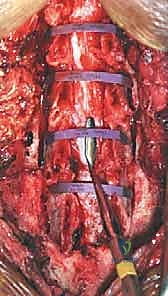

TECH FIG 1 • A. Lamina exposure after subperiosteal dissection and spinous process removal. The dissection should extend laterally to expose the junction of the lateral mass and lamina. Attempts should be made to minimize disruption of the facet capsule. This will decrease long-term postoperative neck pain. Planned lines for opening and hinge trough creation have been marked using electrocautery and marking pen.

<figure class="operative-step-slider my-4 text-center p-3 border rounded shadow-sm bg-light">

TECH FIG 1 • A. Lamina exposure after subperiosteal dissection and spinous process removal. The dissection should extend laterally to expose the junction of the lateral mass and lamina. Attempts should be made to minimize disruption of the facet capsule. This will decrease long-term postoperative neck pain. Planned lines for opening and hinge trough creation have been marked using electrocautery and marking pen.

Subperiosteal Exposure:

- Once the spinous processes are identified, use a Cobb elevator or similar periosteal elevator to perform a meticulous subperiosteal dissection. Our goal is to expose the laminae from C3 to C7.

- Stay in the Midline: This is crucial. The midline is a relatively avascular plane, minimizing bleeding. Work your way laterally, staying directly on bone.

- Lateral Extent: The dissection should extend laterally to fully expose the junction of the lateral mass and the lamina. However, be vigilant: do not extend beyond the midportion of the lateral masses. This is vital to minimize disruption of the facet capsules, which are a common source of postoperative axial neck pain.

- C2 Preservation: Carefully preserve the extensor muscle attachments to the C2 spinous process. Also, ensure the inferior C2 laminar margin is well exposed, especially to visualize the C2-C3 junction.

Spinous Process Amputation (C3-C7): For most laminoplasties, we will amputate the spinous processes from C3 to C7 at their base. This significantly improves our exposure and reduces asymmetric posterior displacement of the paraspinal musculature. These resected spinous processes are valuable; they can be used for bone graft, either for strutting open the lamina or as local bone graft for the hinge side, promoting fusion if needed.